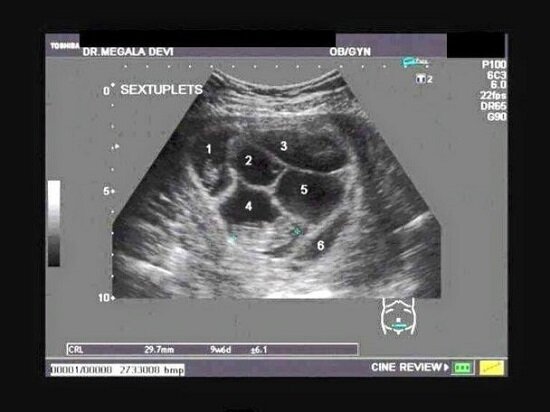

Gdy małżeństwo zgłosiło się na badanie USG, podczas wykonywania zabiegu lekarz zwrócił się do nich z uśmiechem na ustach i słowami „Gratulacje! Spodziewajcie się pięcioraczków!”. Para rzecz jasna nie spodziewała się takiego obrotu spraw, lecz oprócz totalnego zdziwienia na ich twarzach malowało się czyste szczęście. Tymczasem okazało się, że lekarz ma im do przekazania jeszcze jedną wspaniałą nowinę. „A niech mnie!” krzyknął doktor „Widzę szóstego bobasa!”